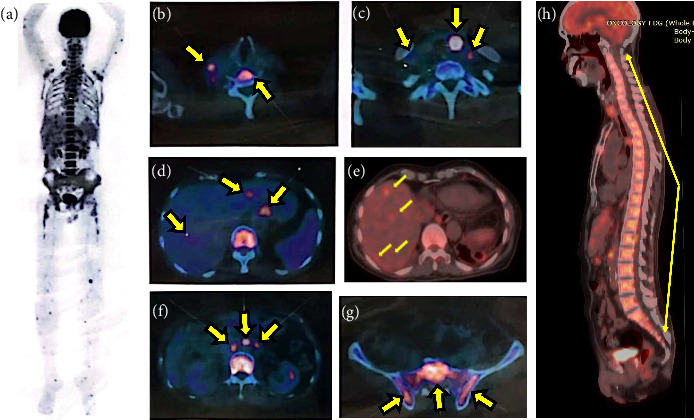

Necrotizing sarcoid granulomatosis (NSG) is a rare disease characterized by granulomatous and necrotic features as well as vasculitis, and it primarily affects the lungs, with occasional extrapulmonary manifestations. The first documented case was in Jakarta, Indonesia. A 71-year-old male presented with prolonged fever, a neck mass, and multiple mediastinal lymphadenopathy. The disease was initially suspected as lung tuberculosis, but a surgical biopsy of the left thyroid lobe confirmed the NSG pattern. Treatment with oral prednisolone led to positive outcomes, as evidenced by radiological improvement at the 3-month follow-up. This case report aims to emphasize the challenges and the importance of clinician awareness in diagnosing NSG.